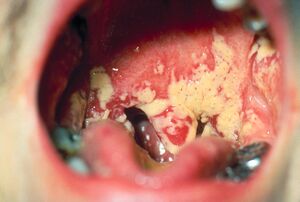

- Oral candidiasis is by far the most common fungal infection that occurs in the mouth. It usually occurs in immunocompromised individuals. Individuals who have undergone a transplant, HIV, cancer or use corticosteroids commonly develop candida of the mouth and oral cavity. Other risk factors are dentures and tongue piercing. The typical signs are a white patch that may be associated with burning, soreness, irritation or a white cheesy like appearance. Once the diagnosis is made, candida can be treated with a variety of anti fungal drugs.[22]